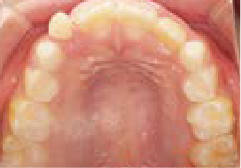

さらに、上からあごの骨を見たところ、中央がくびれた“ひょうたん型”に変形しており、あごの成長にも偏りが見られました。

診断の結果、前歯の中心も少し左にずれており、特に犬歯が生えるスペースが足りない状態でした。